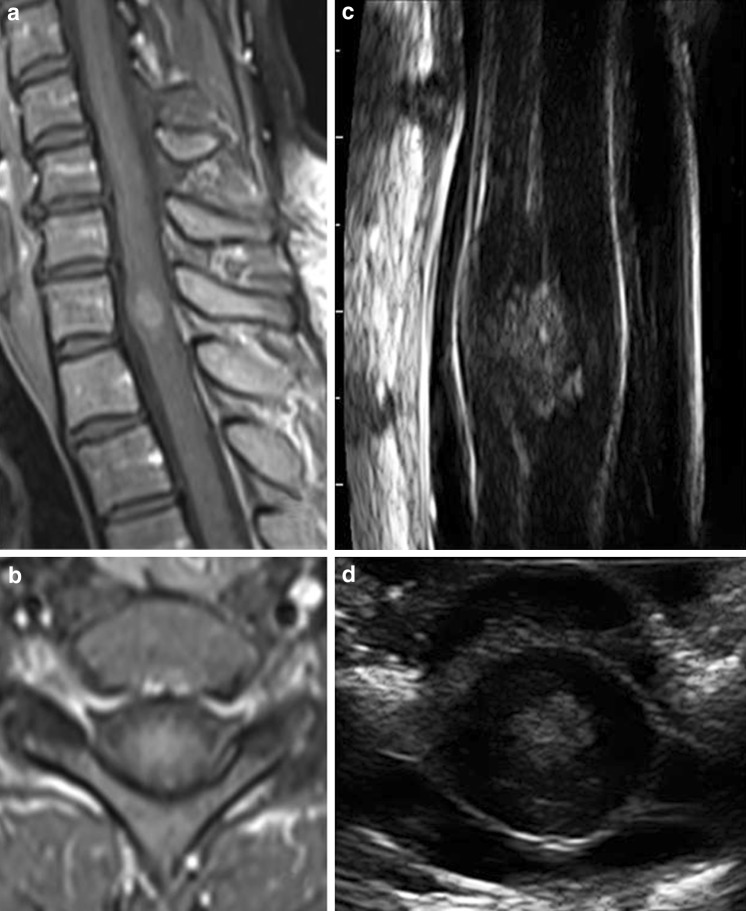

髓内肿瘤:术前T1加权钆增强矢状位(a)和轴位(b)MRI扫描髓内室管膜瘤。术中导航(c、d)的发现与MRI相似,显示脊髓扩大,无明显水肿。中央室管膜也用术中导航很好地暴露了。

资料来源:美国国立卫生研究院医学图书馆(PMC)https://www.ncbi.nlm.nih.gov/pmc/articles/PMC4142127/